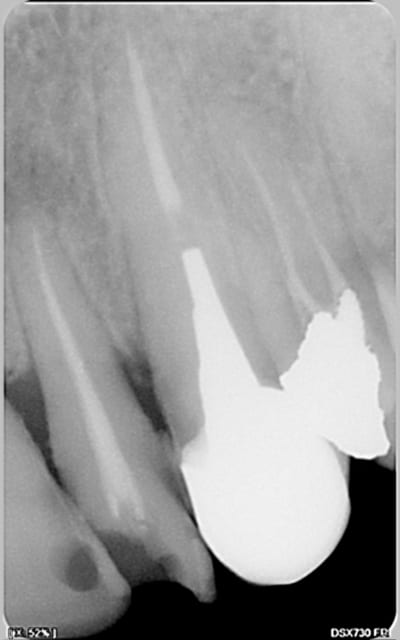

encore des radios,peut-etre assez moyen comme traitement...mais je vu pire...

les dernieres radios. patient en urgence ,abces... il voulait pas extraire la dent. j'ai lui bien explque et il a choisi de essayer de garder la dent. retrait,pas d'isolation avec la digue donc pas de tenon fibree,amalgam et screw post.traitement fait il ya 2 ans je crois.patient fidel de cabinet maintenent.

j'ai jamais utilise en roumanie l'amalgam et ca s'utilise pas du tout dans le cabinet du roumanie.